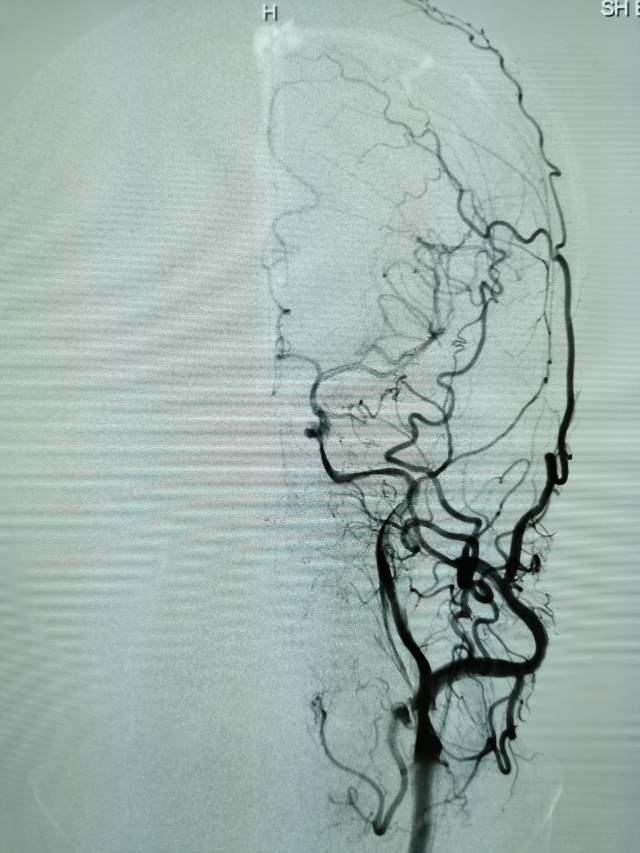

我们全面评估后,基于安全考虑,住院期间先后完成了两次外科干预,帮助患者将已经闭塞的血管重新开通,“满江红”的大脑终于变成了“半江红”,第一次外科干预后,保姆说改变好明显;第二次干预后的第二天,患者眼神明亮、对答如流、思维敏捷、面带微笑,在病房里走来走去,俨然像巡视病房的医生,很是拉风。